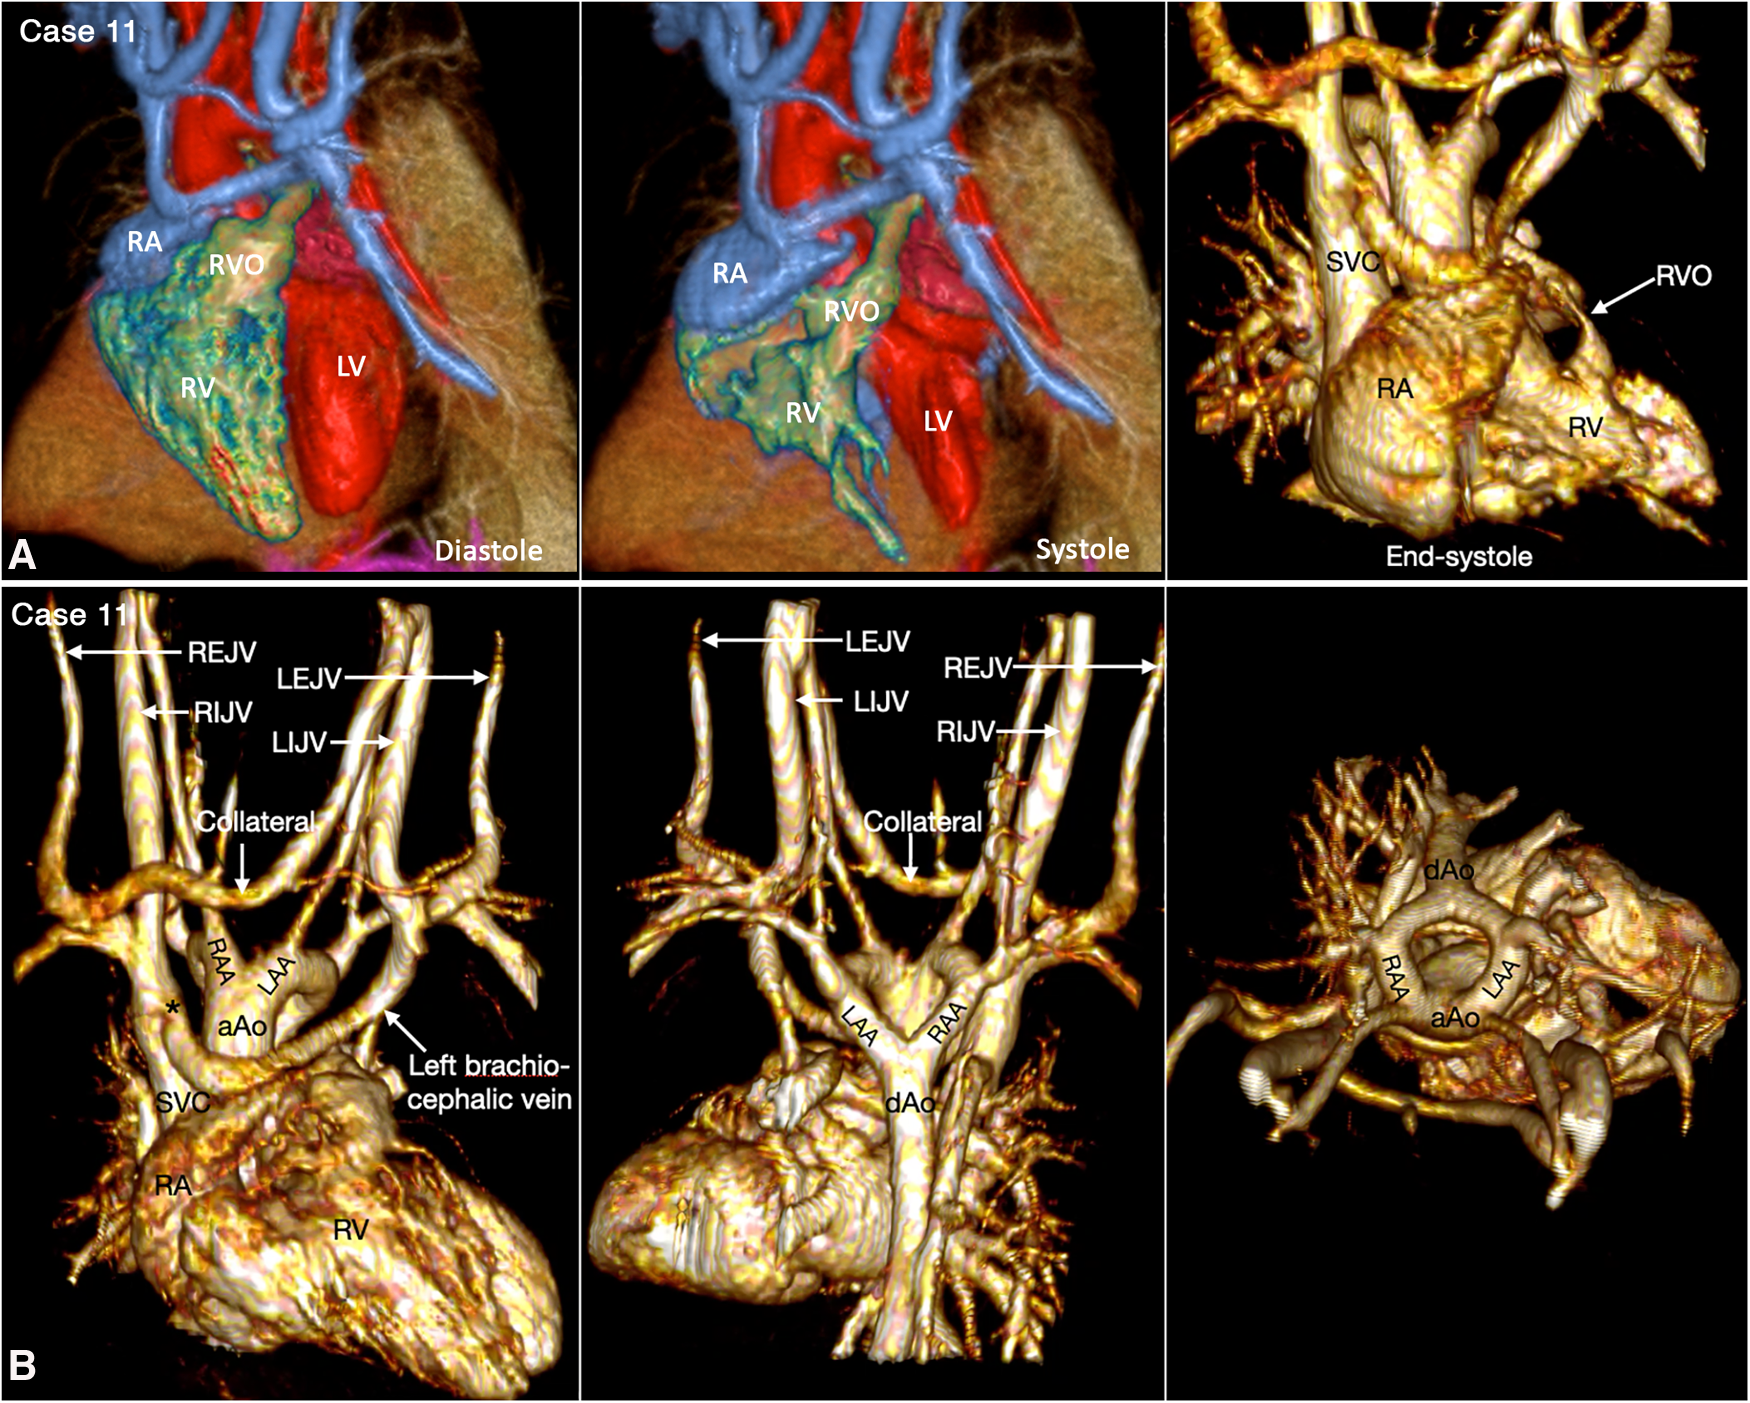

Figure 12

(Case 11). Dynamic right ventricular outflow tract narrowing in a patient with tetralogy of Fallot. (A) Volume rendered (VR) images taken in diastole (left panel) and end-systole (middle and right panel) show severe dynamic subpulmonary right ventricular outflow tract (RVO) narrowing is best appreciated in lateral image taken in end-systole. (B) VR images showing double aortic arch. The left brachiocephalic vein shows narrowing (asterisk) at its connection to the superior vena cava (SVC). A collateral channel is seen between the left internal jugular vein (LIJV) and the right external jugular vein (REJV). aAo, ascending aorta; dAo, descending aorta; LAA, left aortic arch; LEJV, left external jugular vein; LV, left ventricle; RA, right atrium; RAA, right aortic arch; RIJV, right internal jugular vein; RV, right ventricle; VSD, ventricular septal defect.